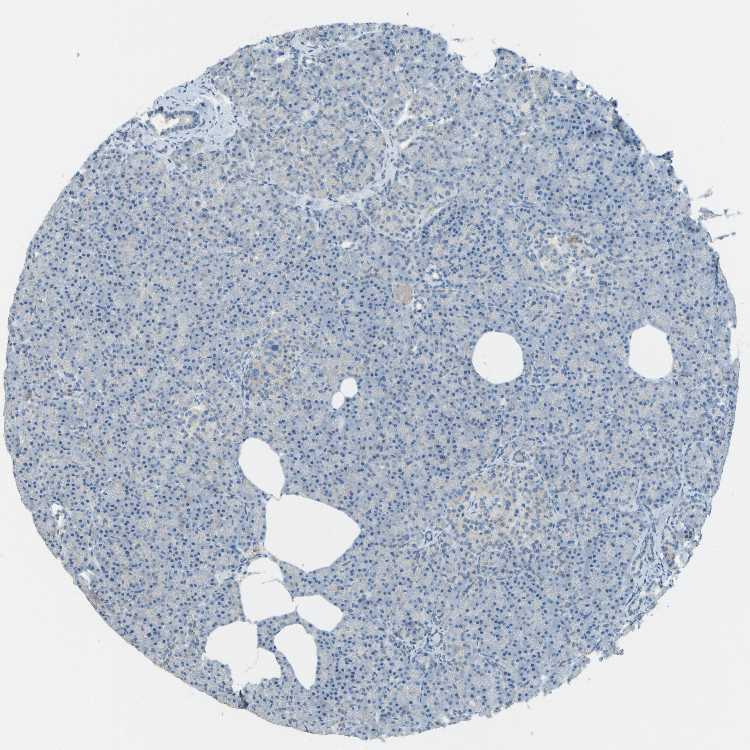

PANCREAS - Antibody stainingi

Antibody staining in the annotated cell types in the current human tissue is reported as not detected, low, medium, or high, based on conventional immunohistochemistry profiling in selected tissues. This score is based on the combination of the staining intensity and fraction of stained cells.

Each image is clickable and will lead to virtual microscopy that enables deeper exploration of all samples and also displays staining intensity scores, fraction scores and subcellular localization as well as patient and tissue information for each sample.

Antibody HPA017140

Exocrine glandular cells Not detected

Pancreatic endocrine cells Low